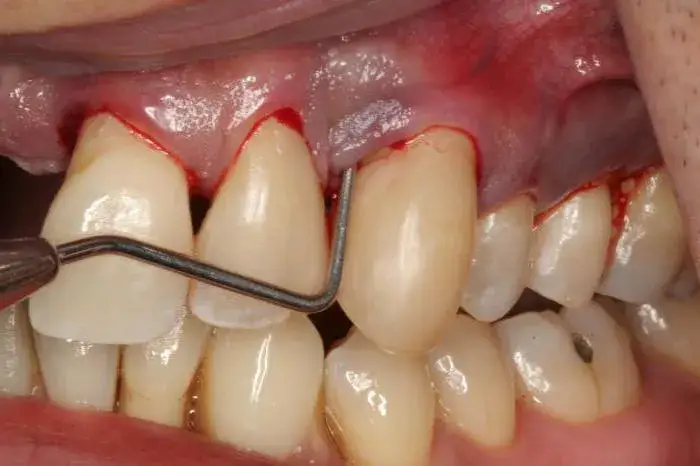

Jednym z pierwszych sygnałów recesji dziąseł są odsłonięte szyjki zębowe. To moment, gdy korzeń zęba staje się widoczny, co może prowadzić do dyskomfortu. Jeśli zauważysz, że Twoje zęby wydają się dłuższe, to może być znak, że dziąsła się cofają.

Nadwrażliwość zębów to kolejny częsty objaw. Może pojawić się ból podczas picia zimnych napojów lub jedzenia gorących potraw. Wrażliwość ta wynika z odsłonięcia korzeni, które nie są chronione przez szkliwo. Warto również zwrócić uwagę na krwawienie dziąseł, które może występować podczas szczotkowania.

Diagnostyka recesji dziąseł zaczyna się od dokładnego badania stomatologicznego. Dentysta ocenia stan dziąseł, mierzy głębokość kieszonek dziąsłowych i sprawdza, czy nie ma oznak stanu zapalnego. To pierwszy krok do postawienia właściwej diagnozy.